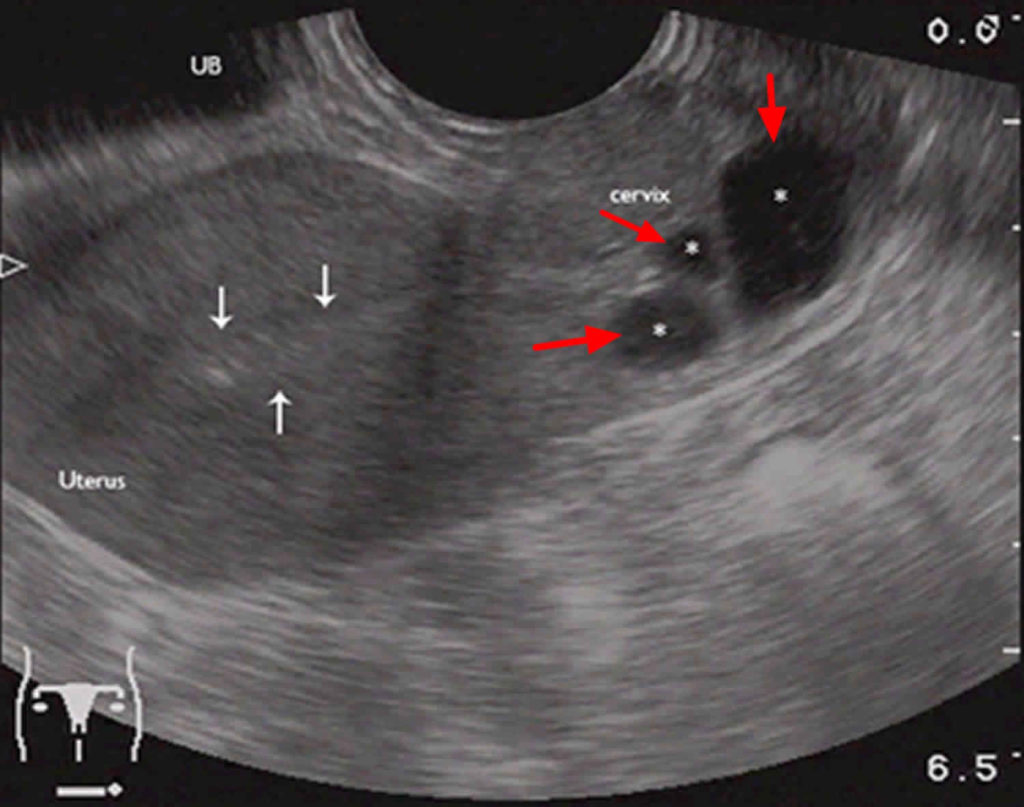

اندازه کیست های نابوتین از چند میلیمتر تا چهار سانتیمتر متغییر است. این کیست ها صاف هستند و به زنگ سفید یا زرد ظاهر میشوند. اما باعث درد، ناراحتی یا علائم دیگر نمیشوند؛ بنابراین احتمالا پزشکتان در طول معاینات معمول لگن متوجه بروز یک یا چند کیست در دهانه رحم شما خواهد شد.

کیست های نابوتین خوش خیم هستند و عموما نیاز به درمان ندارند. در موارد نادر این کیست ها ممکن است بزرگ شوند و شکل و اندازه دهانه رحم را تغییر دهند. اگر کیست نابوتین شما حاد باشد میتواند معاینه معمول دهانه رحم را دشوار یا غیرممکن کند. در این موارد پزشک ممکن است برداشتن کیست نابوتین را به منظور معاینه دهانه رحم توصیه کند.